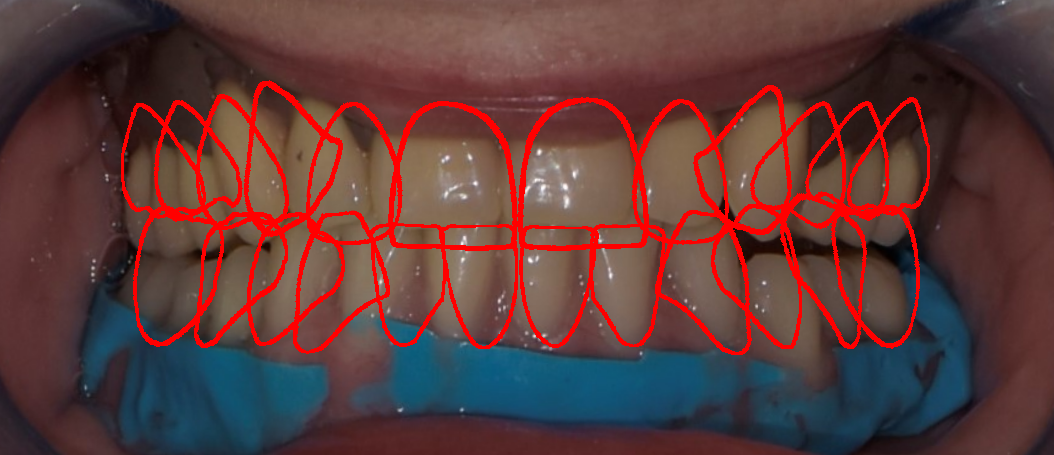

foto 13 match tra scansioni e fotografia

foto 14 outline per definire volumi protesici

foto 15 progetto protesico ultimato

La fase protesica inizia con la ribasatura delle protesi provvisorie per rilevare la corretta anatomia della cresta. Quindi si procede a scansionare con scansione intraorale le impronte ottenute fuori dal cavo orale, poi le protesi provvisorie ribasate ricollocate nel cavo orale e la loro occlusione. Infine, si scansionano le creste edentule dopo aver posizionato gli scan body per tecnica digitale per rilevare la posizione degli impianti. Per la pianificazione sono scattate delle fotografie intraorali ed extraorali per la definizione dei limiti perimetrali del volto al fine di poter eseguire la programmazione del caso tramite il software di previsualizzazione. Le scansioni così ottenute sono poi inviate al laboratorio per la realizzazione di un prototipo delle protesi in prova.